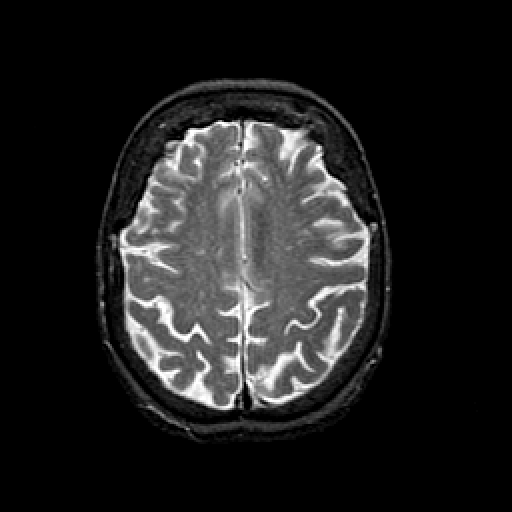

T2-weighted structural MR: Slice 38

Slice 38